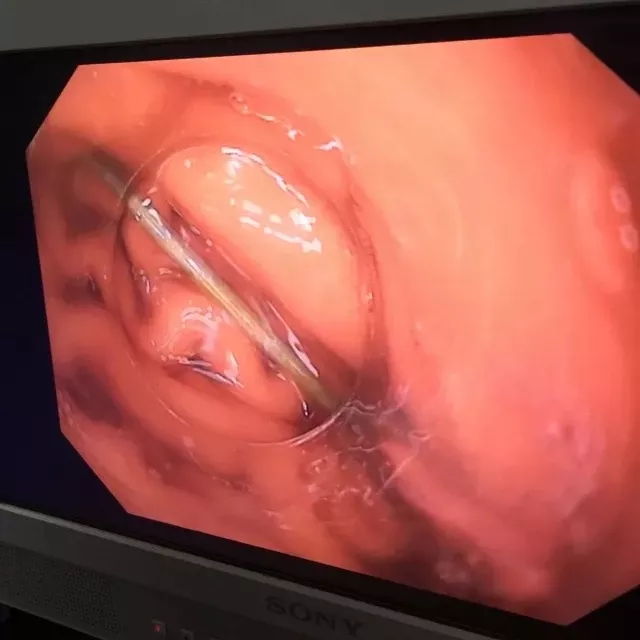

11月21号下午,一名5岁的小朋友在玩耍时误服一颗泡大珠,患儿家长得知后迅速来我院儿外科急诊就诊,考虑泡大珠遇水可膨胀至4-6cm大小,若不慎排入肠道可能引发肠梗阻,需面临开腹手术的风险。儿外科急诊医生立即开通绿色通道,电话通知胃肠镜室医生,胃肠镜室医生在向患儿家属交代病情及相关风险后立即联系麻醉科,待一切准备就绪后在全身麻醉下对患儿行急诊内镜下异物取出术。

进镜后于胃底体交界处可见一蓝色圆形异物(泡大珠),此时泡大珠已膨胀至1.5cm×1.5cm,脆性增加,为防止在取出过程中泡大珠碎裂,不能完整取出可能会对患儿身体造成二次伤害,术中使用了一次性网兜套圈,完整将异物套住,顺利取出。术后,再次观察泡大珠完整,患儿无不适。